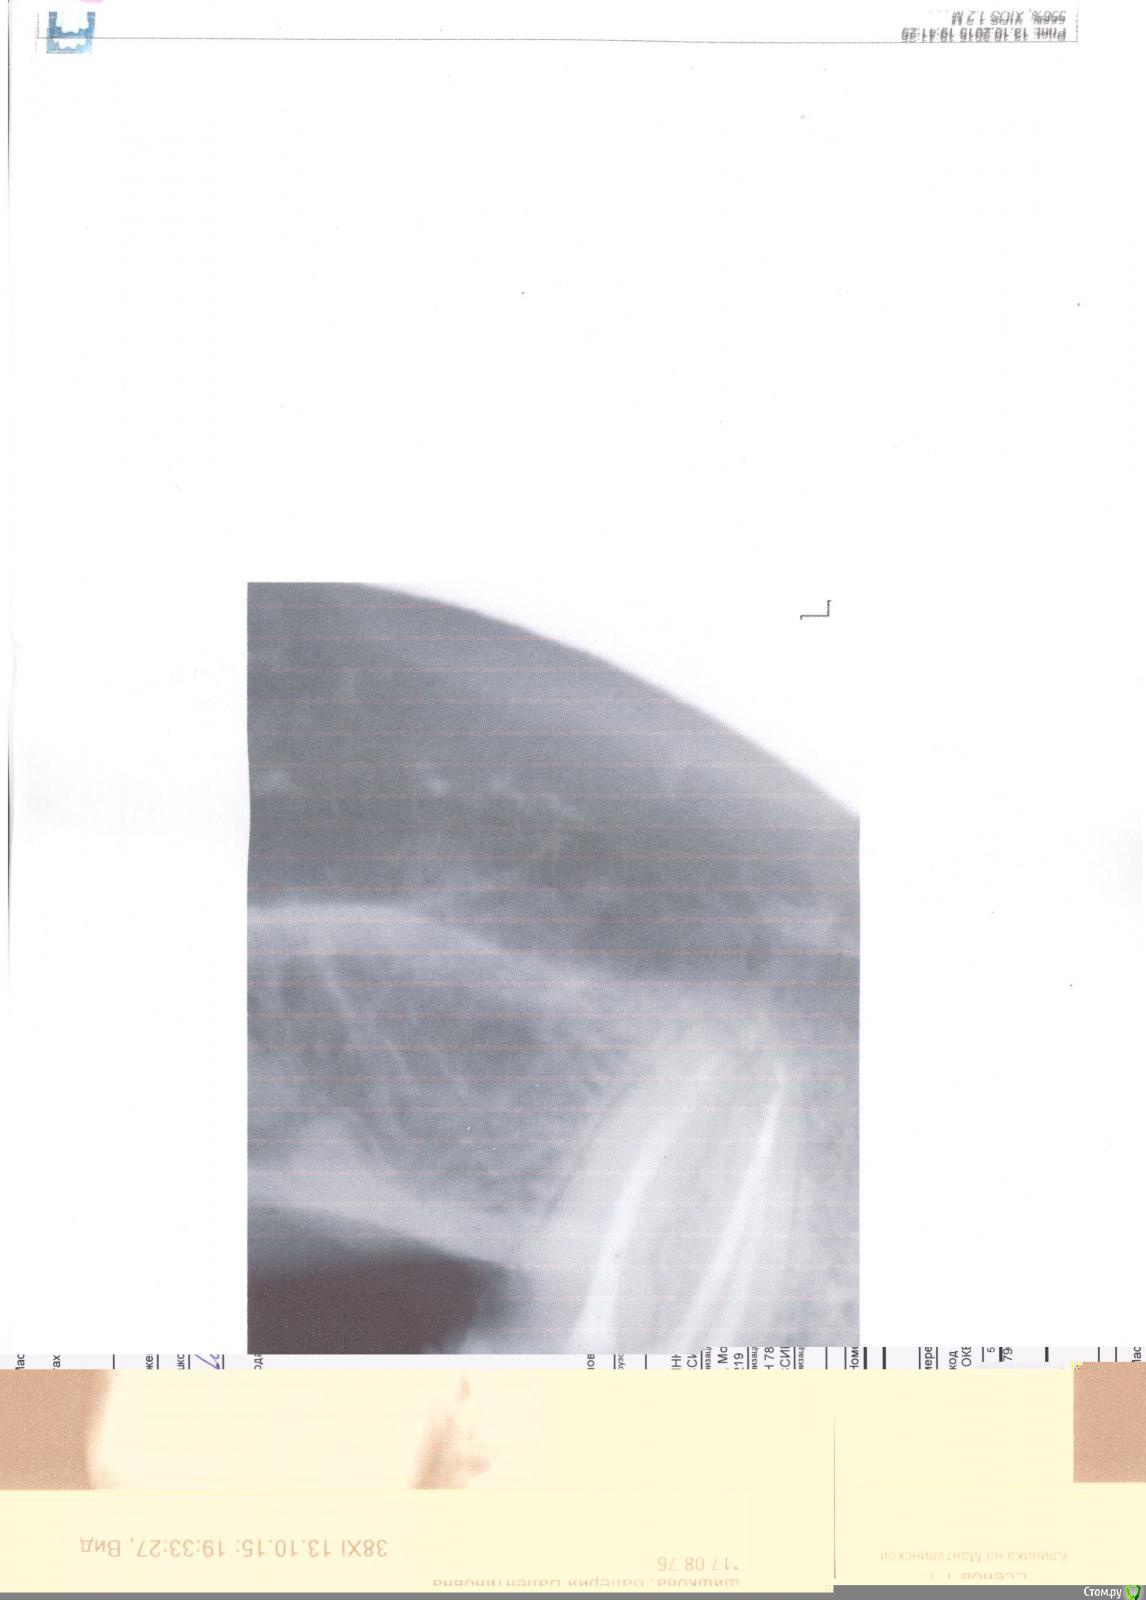

Валерия2 Опубликовано 16 октября, 2015 Поделиться Опубликовано 16 октября, 2015 (изменено) Посоветуйте,что делать, совсем запуталась. У меня неделю назад разрушилась пломбы 7 нижнего зуба, а также его внутренняя стенка обломилась. Была у нескольких врачей-ортопедов в платных клиниках, мнение у них сошлось на том,что необходимо делать вкладку и на нее коронку. Все говорили,что работа сложная,нет никакой гарантии. Сегодня зашла со снимком в районную -Он посмотрел на снимок,и сказал ,что так как корни без трещин (возможно дословно я неправильно пишу,но так как поняла)и соединены ложем,то здесь нельзя ставить вкладку,так как при обтачивании под вкладку пройдут это нижнее ложе и корни разойдутся,тогда только под удаление. Теперь совсем не знаю ,что делать,какое решение принять, очень хочу сохранить этот зуб,подскажите. Причем один из врачей меня предупредил,что если мне предложат сделать коронку - не делайте,совсем зуб потеряете. И тем не менее ...внушает мне доверие, он говорит,что делать нужно только металл,так как под него совсем мало снять придется.Прикрепляю снимок Изменено 16 октября, 2015 пользователем IvanK Ссылка на комментарий

Валерия2 Опубликовано 16 октября, 2015 Автор Поделиться Опубликовано 16 октября, 2015 есть снимок, который выложила - он распечатан на бумаге, сегодня заберу ренген -выложу(делали на пленке, как раньше/ маленький, наверно только панорамный подойдет что-либо понять?) Ссылка на комментарий

Валерия2 Опубликовано 16 октября, 2015 Автор Поделиться Опубликовано 16 октября, 2015 Думаю, как сделать фото, сейчас попробую, ситуация визуально такая, защечная стенка есть, и на ней висит часть оставшейся пломбы, внутренняя стенка обломана, облом уходит вниз под десну, так вот, врачи платных клиник утверждают,что так как разрушение более 50%, то только вкладка (но не дают вообще никакой гарантии-обошла троих, и ,честно говоря меня интуитивно останавливает их быстрый диагноз) в районной доктор,посмотрев, сказал,как я уже писала выше, объяснил,что он бы не взялся делать вкладку,так как велика вероятность надлома ложа,а делать нужно только металлическую коронку. Я задала вопрос, будет ли к чему прикрепить коронку, так как внутренняя стенка сломана неизвестно где, он говорит-это наши проблемы,укрепить можно, но только металл, так как мало сточим. Извините, просто вопрос для меня животрепещущий. Я почему в районную пошли, денег я готова заплатить, но за хорошую работу, а если тебе говорят,что нет гарантии(то есть врач страхуется заранее,так я понимаю, а если что скажет, ну я же предупреждал..) сейчас попробую фото сделать. Спасибо ,что пытаетесь помочь) Ссылка на комментарий

Валерия2 Опубликовано 16 октября, 2015 Автор Поделиться Опубликовано 16 октября, 2015 Спасибо за ответ. скажите, а возможно поставить коронку без вкладки. я так понимаю,что коронка крепится на штифты (ну как раньше делали+ мет коронка) . Я не имею в виду технически, скорее всего возможно, а насколько долговечно. Врач сказал,что простоит сколько сам зуб простоит и объяснил так, что когда начнут каналы проходить для вкладки, их расширят и возможно сломают перемычку между корнями- тогда только под удаление (видимо по снимку он увидел,что она истончена) , а все врачи помоложе - за вкладку, причем мне сказали неразборную, -будут вводить в 2 канала. Ссылка на комментарий

IvanK Опубликовано 16 октября, 2015 Поделиться Опубликовано 16 октября, 2015 Коронка одевается на "что-то", а у Вас почти весь зуб состоит из пломбы, а другая часть откололась... Если скол ниже уровня десны, то перспектив у зуба не много. . Ссылка на комментарий

DR.P Опубликовано 16 октября, 2015 Поделиться Опубликовано 16 октября, 2015 В вашем случае если судить по предоставленным фотографиям, только вкладка + коронка. Но хочется увидеть на сколько глубоко с язычной стороны. Ссылка на комментарий